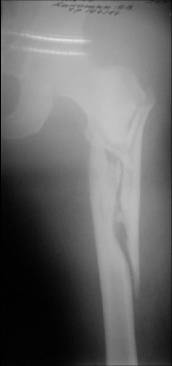

Few days ago I have posted an x-ray of severely comminuted Trochenteric # of Lt. Femur with sub-trochenteric extension of a male patient aged 65 years for opinion of fixation. Eight of you have kindly replied........

I choose Long Gamma Nailing and did it on 24.1.2006.